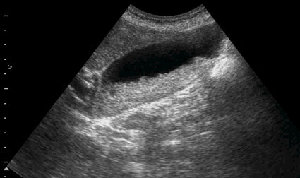

Женщина 59 лет с болями в подребрье справа.

- Повторная сонограмма через сутки.

Думаю, что это варианты трансформации коллоидальной устойчивости самой желчи,точнее слажа, т.е.фазовые переходы: фезикулярный агломерат - жидкий кристалл - истинный кристалл и обратно

Разделяю точку зрения высказанную выше. Dynamical US control of GB sludge formation stages.

Да, скорее всего, больной был на голоде.